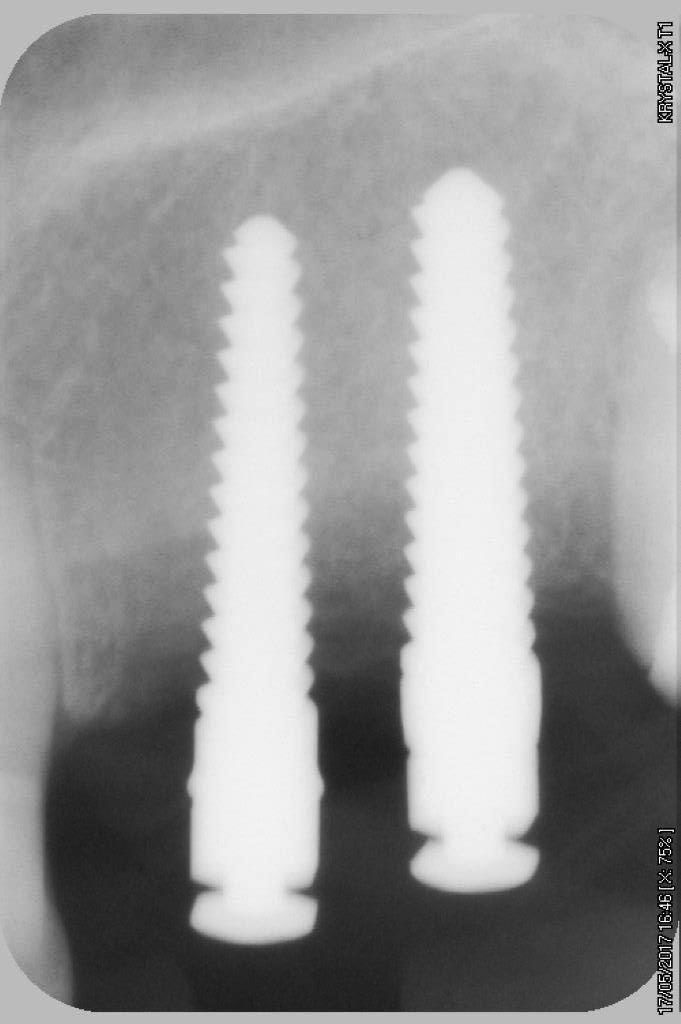

petit cas sympa ancien bridge très mobile....plutôt que d'extraire 25, j'ai déposé la couronne, retraité la dent stabilisation pendant deux mois puis séance d'ostéotension et ce jour pose de deux axioms PX 34120 après expansion...

comme je n'ai pas fait de décharges osseuse en vestibulaire, j'ai effectivement travaillé toute la longueur de la crête, mais, là j'ai ôtè les expanseurs avant de visser les implants car ce sont des PX qui ont un apex assez fin, pour des regular j'aurais pratiqué différemment.

par contre je suis passé par le stade implants lisse (34100 et 34120)

par contre les axioms doivent être posé en sous crestal, ce qui est fait ici, avec sans doute comme souvent une nécessitè d’ostéotomie, lors de la mise en charge, car il est fréquent que le col implantaire soit recouvert.